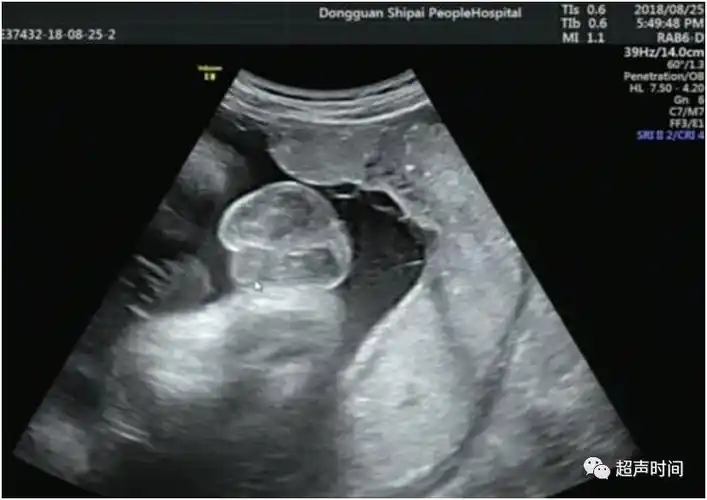

胎儿严重结构畸形的产前筛查与诊断:从中孕期提前到早孕期

皮肤开始出现毛囊,肝脏开始活动头部占胎儿身长的一半外部生殖器官